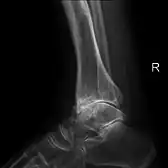

Diagnosis is made with reasonable certainty based on history and clinical examination.[52][53] X-rays may confirm the diagnosis. The typical changes seen on X-ray include: joint space narrowing, subchondral sclerosis (increased bone formation around the joint), subchondral cyst formation, and osteophytes.[54] Plain films may not correlate with the findings on physical examination or with the degree of pain.[55]

Severe osteoarthritis and osteopenia of the carpal joint and 1st carpometacarpal joint